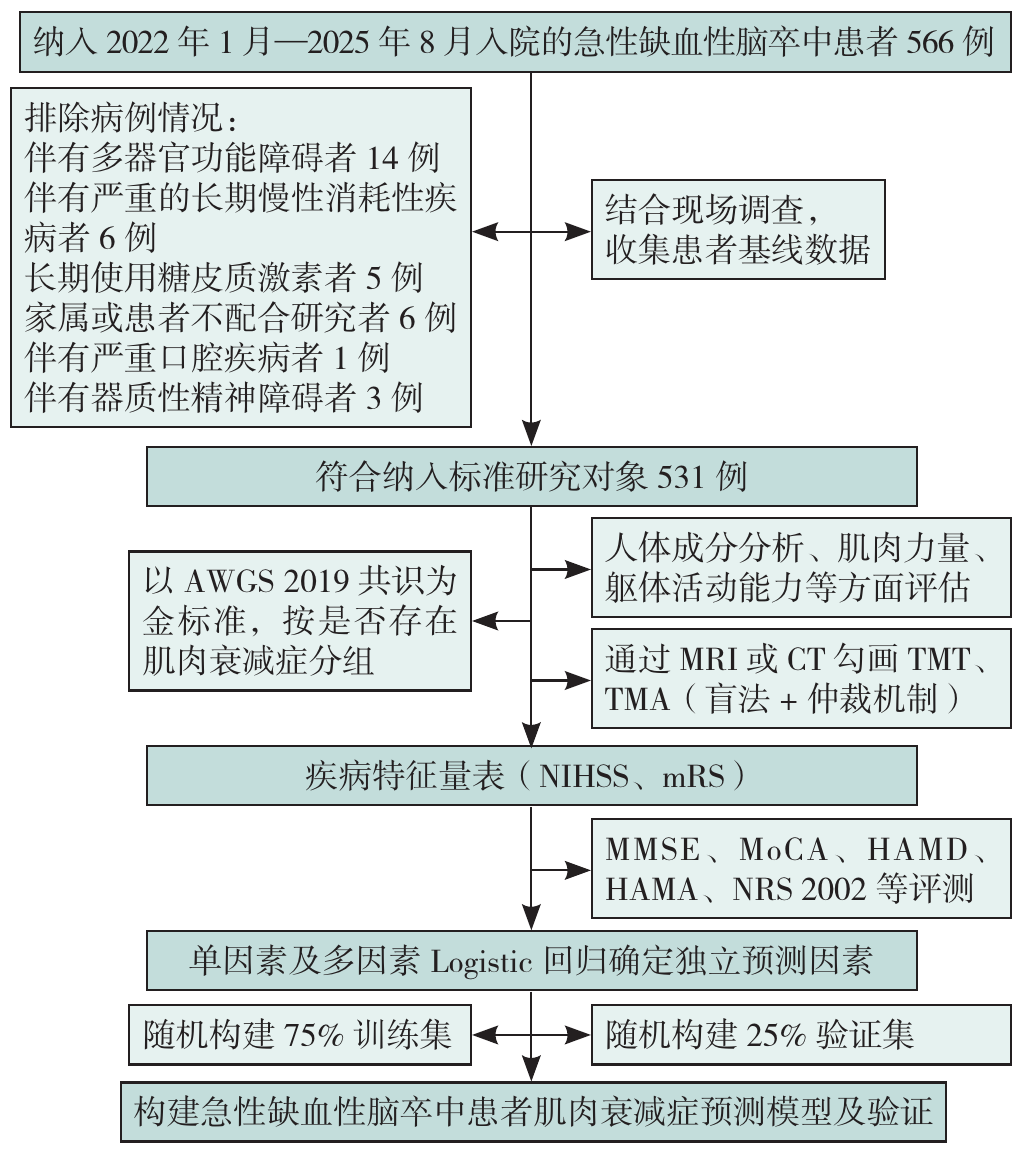

图2 研究流程图注:AWGS=亚洲肌肉减少症工作组,TMA=颞肌横截面积,TMT=颞肌厚度,NIHSS=美国国立卫生研究院卒中量表,mRS=改良RANKIN量表,NRS 2002=营养风险筛查量表,MMSE=简易精神状态检查量表,MoCA=蒙特利尔认知评估量表,HAMA=汉密尔顿焦虑量表,HAMD=汉密尔顿抑郁量表。

Figure 2 Research flow chart